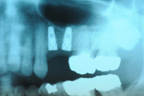

左下顎植入兩顆牙根。

X光片顯示植體位置。